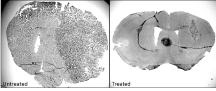

The lab of Associate Professor Emma Wilson collaborates extensively with lecturer Jack Eichler of the chemistry department to teach undergraduates about glioma and develop novel drug therapies from design and synthesis through to in vitro and in vivo testing. Glioblastoma multiforme is a devastating cancer that even with all available therapies gives a life expectancy of ~ 18 months. This collaboration has discovered several novel metal based compounds and associated ligands that have significant anti-glioma efficacy against murine and human glioma cell lines and one in particular that demonstrates significant in vivo efficacy. Further work is being conducted to understand the mechanism of action of these compounds.